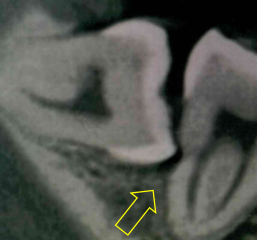

左上奥歯が割れています。一般的なレントゲンではわかりません。

CTでは破折線がはっきり見えます。患者様も納得しやすいです。